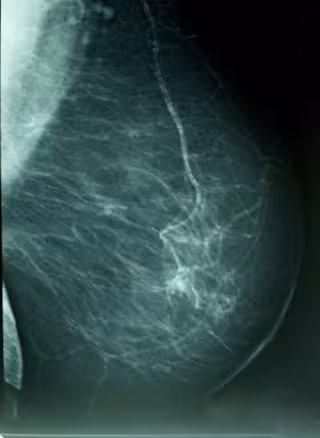

Cáncer De Mama, Densidad Mamográfica

WIKIPEDIA/A. AVENDAÑO

Por eso, ha destacado las campañas de prevención y de diagnóstico precoz de la Región de Murcia y ha aconsejado a todas las mujeres comprendidas entre los 50 y 70 años que se hagan una mamografía.

Tras lo que ha hecho un llamamiento para que todas las mujeres de esas edades se hagan una mamografía porque el diagnóstico precoz "consigue que el tumor se detecte antes de que se palpe", es "la mejor manera de poder luchar contra esta enfermedad" y tiene mucha posibilidad de curación. Además, ha apostillado, en los últimos bienios, se han diagnosticado más de 235 casos en la campaña de prevención.